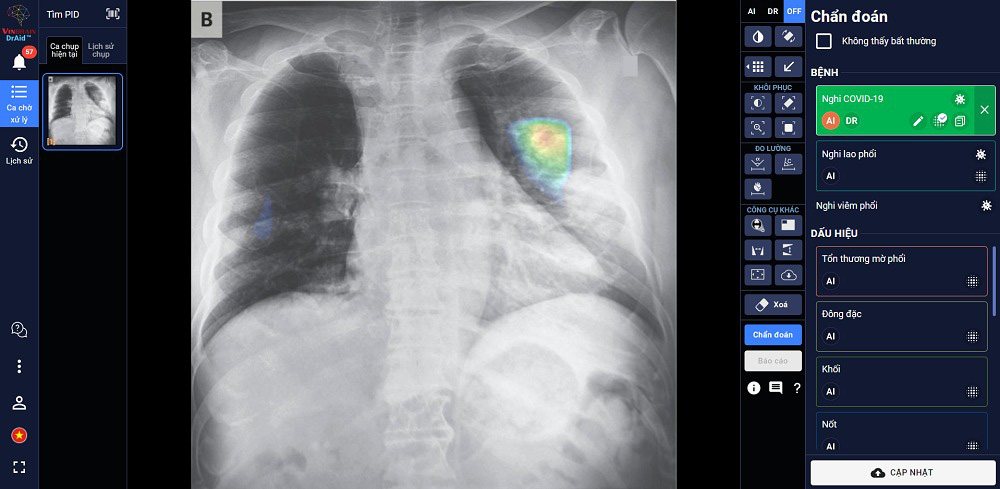

"DrAid for Radiology"– AI Trợ lý Bác sĩ cho Chẩn đoán hình ảnh y tế là sản phẩm đầu tay của VinBrain và cũng là sản phẩm AI hoàn chỉnh đầu tiên của y tế Việt Nam ra mắt phiên bản đầu tiên vào ngày 14-06-2020.

Theo đại diện đơn vị này, sản phẩm có khả năng phát hiện, sàng lọc trên 21 dấu hiệu bất thường và bệnh lý về Phổi – Tim – Xương trong vòng 5 giây với độ chính xác trên 89%; đồng thời có thể chia sẻ kết quả chẩn đoán thông qua QR code hoặc đường link.

"Đặc biệt, sản phẩm có khả năng tự cảnh báo COVID-19, kể cả các trường hợp không có triệu chứng hoặc tổn thương phổi nhẹ dựa trên X-quang ngực thẳng, kết hợp cùng xét nghiệm PCR giúp nâng cao độ chính xác, giảm thiểu tình trạng âm tính giả... DrAid cũng nổi bật với tính năng "Hỏi ý kiến Bác sĩ thứ 2 (từ xa)".

Thông qua việc chia sẻ hình ảnh trực tiếp từ DrAid, bác sỹ có thể hội chẩn từ xa với đồng nghiệp hoặc tham khảo ý kiến của các chuyên gia đầu ngành mà không bị ảnh hưởng bởi rào cản địa lý", đại diện đơn vị này nhấn mạnh.

Đại diện đơn vị này cũng cho biết DrAid được Ban giám khảo ACM SIGAI đánh giá cao vì sản phẩm đã kết hợp và ứng dụng những kỹ thuật tiên tiến nhất trong lĩnh vực trí tuệ nhân tạo như phân loại nhiều lớp, suy luận theo cấu trúc cục bộ đến tổng quan, học chủ động, đào tạo đối nghịch, mạng nơ ron tích chập phức hợp, nhận dạng giọng nói cho chỉnh sửa báo cáo Y tế tự động, khoanh vùng tổn thương trên ảnh Y tế với kiến thức máy học sử dụng công nghệ cao AI dựa trên mô hình với hàng trăm triệu tham số điểm ảnh (pixel) và dữ liệu lớn hàng triệu ảnh với mỗi ảnh có hàng triệu điểm ảnh (pixel), cùng nhiều kỹ thuật khác tạo nên một dịch vụ trí tuệ nhân tạo phục vụ Y tế toàn diện.

Giao diện DrAid - phần mềm AI có khả năng phát hiện, sàng lọc trên 21 dấu hiệu bất thường và bệnh lý về Phổi – Tim – Xương trong vòng 5 giây với độ chính xác trên 89%. Ảnh: B.C

Là sản phẩm duy nhất được trao giải năm 2021, DrAid đã chứng minh năng lực cũng như vị thế tiên phong của VinBrain trong ứng dụng AI vào chăm sóc sức khoẻ tại Việt Nam, khẳng định khả năng cạnh tranh ngang bằng với các sản phẩm công nghệ cùng ngành trên thế giới.

Hiện DrAid đang được triển khai tại 84 bệnh viện và cơ sở y tế Việt Nam, bao gồm các bệnh viện hàng đầu như Bệnh viện TW Huế, Bệnh viện Đại học Y Dược TP HCM, Hệ thống Bệnh viện Đa khoa Quốc tế Vinmec, Bệnh viện TW Thái Nguyên….